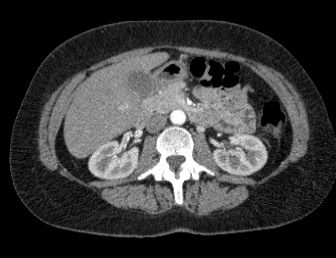

Мультиспиральная компьютерная томография (МСКТ) брюшной полости и забрюшинного пространства относится к современным лучевым методам исследования, с помощью которого можно оценить состояние органов брюшной полости (печени, желчного пузыря, поджелудочной железы, селезенки), забрюшинного пространства с расположенными в нем почками, надпочечниками, мочеточниками и прилегающих к ним кровеносных сосудов и лимфатических узлов.

С помощью мультиспиральной компьютерной томографии проводятся послойные рентгеновские снимки исследуемой области с толщиной среза от 0,5 мм. Затем полученные данные преобразуются в цифровые трехмерные модели органов и систем в мельчайших подробностях.

При подозрении на опухоли, воспалительные процессы, гнойные очаги назначается КТ брюшной полости и забрюшинного пространства с внутривенным болюсным контрастированием. Для этого пациенту внутривенно вводится рентгеноконтрастное вещество на основе йода. Благодаря усиленному кровоснабжению, которое обычно наблюдается в патологических очагах, препарат накапливается в структуре патологических образований и помогает врачу-рентгенологу выявить изменения внутренних органов.

Метод контрастирования помогает максимально точно выявить очаг патологии уже на начальной стадии, а также установить его локализацию, точные размеры, форму и особенности кровоснабжения. Возможности мультиспиральной компьютерной томографии позволяют выполнить своевременную диагностику заболеваний внутренних органов, от чего напрямую зависит эффективность лечения.